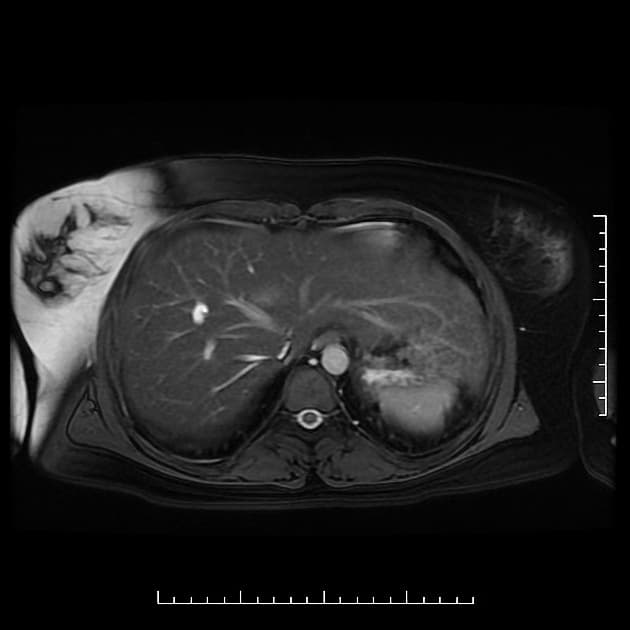

Coronal 3D T2 MIP

MRCP

- Có giãn dạng thoi của ống gan chung và ống mật chủ (common hepatic and common bile ducts). Mức độ giãn kéo dài đến tận vị trí nối với ống tụy chính.

- Vị trí nối bất thường cao giữa ống tụy và ống mật chủ (CBD), kèm theo đoạn chung dài bất thường.

Hình ảnh đặc trưng của nang ống mật chủ type I theo phân loại Todani. Tình trạng này đi kèm với dị dạng nối bất thường giữa đường mật và đường tụy type b (không tắc nghẽn) – có thể là yếu tố thuận lợi dẫn đến sự hình thành nang ống mật chủ.

Nang ống mật chủ - type I (choledochal cyst - type I)